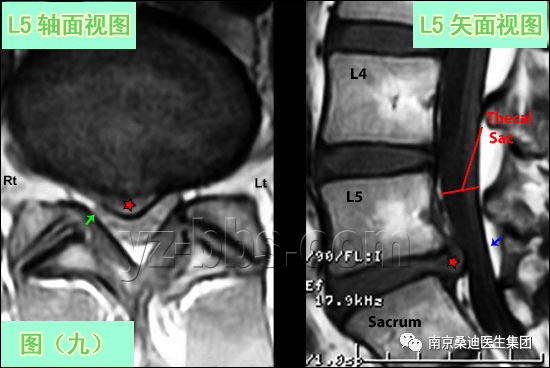

图(9)展示的是一个大的9mm的突出(红星)的T1轴状面及矢状面图。 突出物已经完全将右侧过往神经根S1(图像左侧)遮盖掉(看不到),并将其挤压到椎板(小绿箭头)。在轴状面及矢状面图(蓝箭头与红五星之间)可观察到硬膜囊有来自这个大的突出的中重度压迫。 此患者是一个24岁的年轻人,他已经避免了手术,表现良好。注意看他的椎管要比图10和11中年轻人的椎管小得多,大的椎管要远比小椎管能容忍腰椎间盘突出症。  考试了~看看我们现在都会了什么!